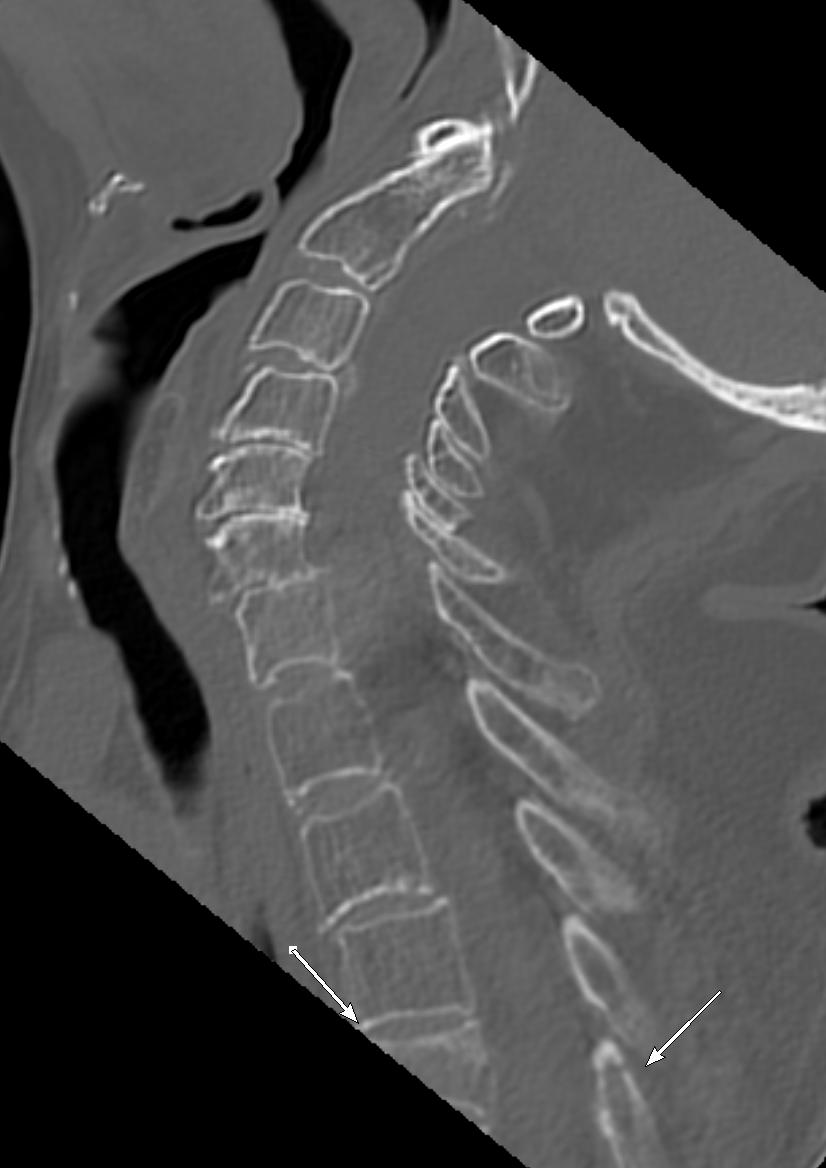

#easytomiss fracture of a bifid spinous process#spine#trauma#radiology#radres This fracture can be overlooked if you are focusing only on sagittal images#EMRad#FOAMrad#FOAMed@NASSspine https://bit.ly/32bT4VX pic.twitter.com/b0g3MRwzhf